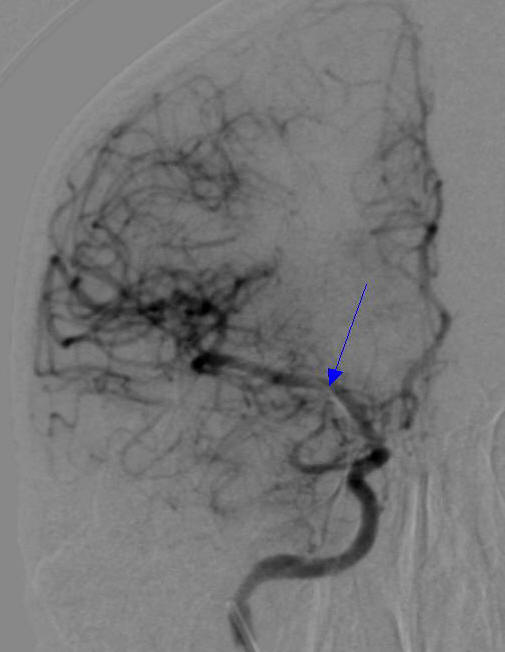

病例1 - 13: 一口气"唱"血管造影诊断_______测试

病例1